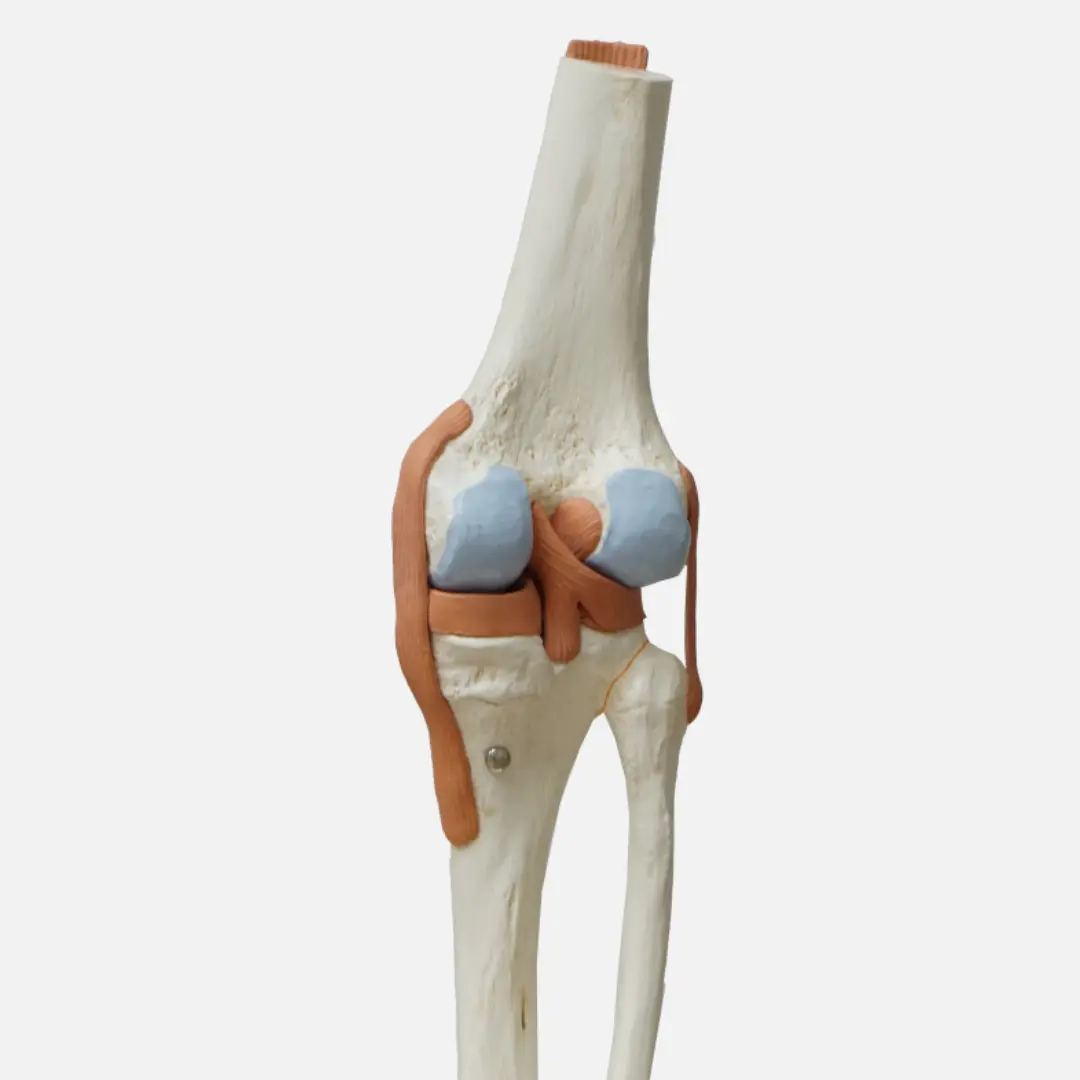

무릎 연골 손상의 원인은 다양합니다. 가장 흔한 원인 중 하나는 퇴행성 변화로 인한 관절염이에요. 나이가 들면서 연골이 점차 닳아 없어지기 때문이죠. 과도한 운동이나 무리한 활동 또한 연골 손상의 주요 원인이 될 수 있습니다. 특히 반복적인 충격이 가해지는 운동이나 갑작스러운 방향 전환은 연골에 부담을 줄 수 있습니다.

스포츠 외상으로 인한 직접적인 충격도 연골 손상을 유발할 수 있습니다. 축구, 농구 등 격렬한 운동 중 무릎 부위에 가해지는 강한 충격은 연골 파열로 이어질 수 있습니다. 이 외에도 비만으로 인한 무릎의 과부하, 잘못된 자세, 유전적인 요인 등이 복합적으로 작용하여 연골 손상을 일으킬 수 있습니다. 드물게는 감염이나 자가면역 질환이 연골 손상의 원인이 되기도 합니다. 따라서 정확한 원인을 파악하는 것이 중요하며, 이를 통해 적절한 치료 및 관리 방법을 찾을 수 있습니다.